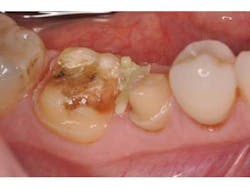

Before preparing the tooth surfaces for bonding, it was noted that the interproximal gingival col showed evidence of mild gingivitis (Fig. 4). This is not an infrequent problem, because patients may not maintain the same levels of hygiene around provisional restorations as they would around natural teeth. In this case, the splinted provisional crowns were unable to be flossed and likely contributed to the gingival irritation. A hemostatic paste (Traxodent, Premier) was applied to quell the bleeding (Fig. 5). This paste sets quickly and is able to maintain its position while further steps are taken.